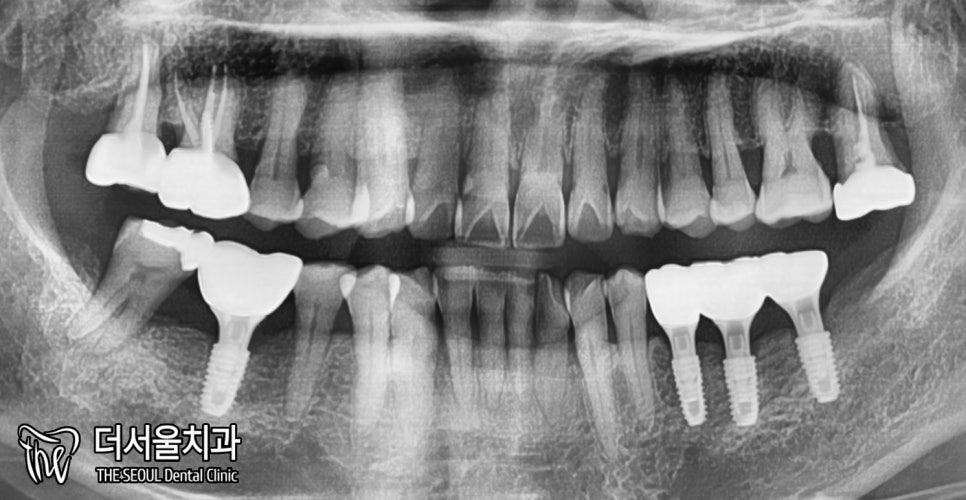

환자분 구내는 어떤 상태일까요?

성남 치과 의원은 먼저 눈으로 살펴봤습니다.

아래를 보면 36, 37, 46번 어금니가 없네요.

그런데 35번은 또 치근만 남아있습니다.

발치할 수밖에 없겠네요.

또, 잇몸뼈가 많이 없습니다.

얇아진 부분을 볼 수 있죠?

아마 치아가 없어진지 오래 되었을 겁니다.

여쭤봤는데 10년이나 두고 있으셨네요.

좀 더 자세히 체크하기 위하여

엑스레이를 찍어봤습니다.

높이는 그렇게 내려가지 않은 것으로 보여집니다.

다만, 너비가 줄어들었던거죠.

아래 임플란트 수술 시,

꼭 주의해야 되는 하치조신경관.

이것과 가깝지는 않은 듯 보였습니다.

엑스레이를 찍어서

확실하게 잘 붙었는지 확인해줍니다.

튼튼하게 잘 식립되었네요. ^^